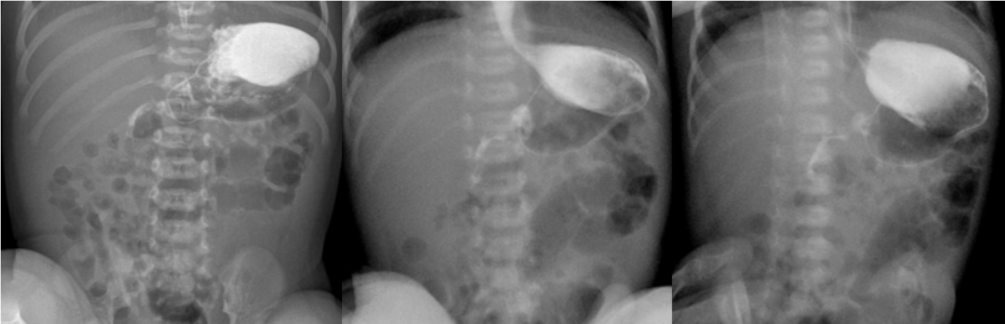

Рисунок 2 - Ребенок возрастом 5 дней, пассаж контрастного препарата

Примечание: процесс осуществления поворота, визуализируется первая и вторая часть двенадцатиперстной кишки, третья часть отчетливо не визуализируется

Рисунок 3 - Ребенок возрастом 5 дней, пассаж контрастного препарата

Примечание: в левом верхнем отделе брюшной полости визуализируется проконтрастированный проксимальный отдел тонкой кишки